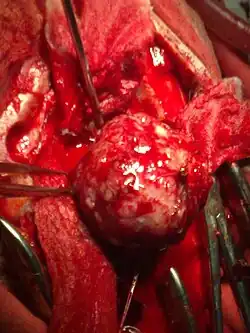

Хирургическое лечение

Хирургическое лечение опухолей головного и спинного мозга является основным, наиболее эффективным методом, однако удаление опухоли из ткани мозга представляет значительную трудность. Каждое такое вмешательство — это сложная нейрохирургическая операция. Так как хирургу необходимо иссечь опухоль в пределах здоровых тканей (чтобы избежать рецидива), то каждая такая операция травматична, а зачастую и вовсе невозможна из-за больших размеров опухоли или её локализации в жизненно важных участках мозга. В зависимости от размеров, локализации, типа опухоли, состояния больного принимается решение о необходимости проведения операции, объёме оперативного вмешательства и способе его проведения. Применение современной лазерной и ультразвуковой техники в хирургии опухолей головного мозга позволило несколько повысить её эффективность. Конкретный путь вмешательства и метод его осуществления индивидуален и зависит от локализации опухоли, её размеров и клеточного состава[8].